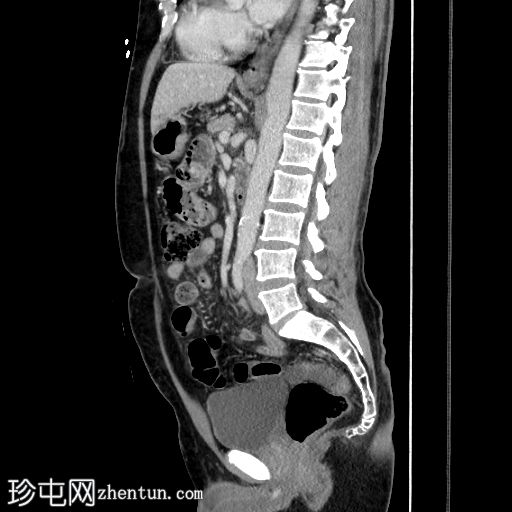

CT

矢状位增强扫描(门静脉期)

阑尾扩张、增厚、强化,可见少量管腔外气体。右下腹及盆腔可见无序液体(伴有少量下垂钙化灶)及条索状改变。未见其他急性期征象。

本病例是阑尾炎早期穿孔的典型病例,仅可见少量管腔外气体,初次检查可能难以发现,且盆腔积液量较预期。盆腔内少量分层钙化灶可能是游离阑尾粪石,也可能是慢

性病

变(例如既往大网膜垂扭转所致)。